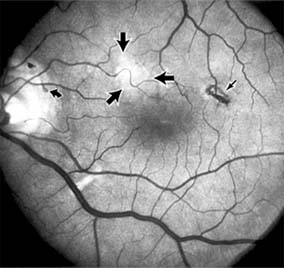

Nonexudative age-related macular degeneration is characterized by variable degrees of atrophy and degeneration of the outer retina, retinal pigment epithelium, Bruch's membrane and choriocapillaris. Of the ophthalmoscopically visible changes in the retinal pigment epithelium and Bruch's membrane, drusen are the most typical (Figure 10-1). Drusen are discrete, round, yellow-white deposits of variable size beneath the pigment epithelium and are scattered throughout the macula and posterior pole. With time, they may enlarge, coalesce, calcify, and increase in number. Histopathologically, most drusen consist of focal collections of eosinophilic material lying between the pigment epithelium and Bruch's membrane; they therefore represent focal detachment of the pigment epithelium. In addition to drusen, clumps of pigment irregularly dispersed within depigmented areas of atrophy may progressively appear throughout the macula. The level of associated visual impairment is variable and may be minimal. Fluorescein angiography demonstrates irregular patterns of retinal pigment epithelial hyperplasia and atrophy. Electrophysiologic testing in most patients is normal.

Figure 10-1

Figure 10-1: Age-related macular degeneration with discrete (small arrow) and large confluent (large arrow) macular drusen.